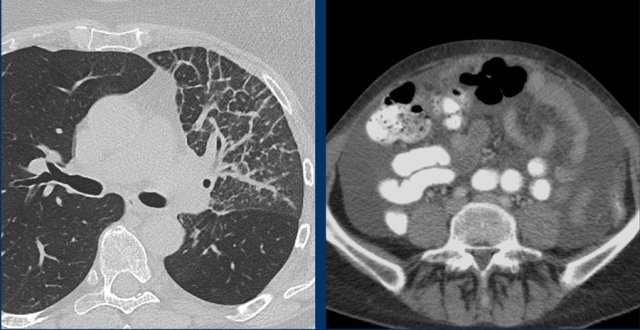

The CT images in the arterial and portovenous phase of a 71-year-old male show liver metastases of a neuro-endocrine tumour of the esophagus.

Note that the hypervascular rim is better appreciated in the arterial phase.

The large hypervascular rim is included in the measurement of the largest diameter.

The CT images of a 82-year-old male show liver metastases of a GIST at baseline (arrowheads).

All metastases decrease somewhat in size after treatment with imatinib, but the most remarkable difference is a decrease in density.

This is considered to be a good response according to the Choi criteria.